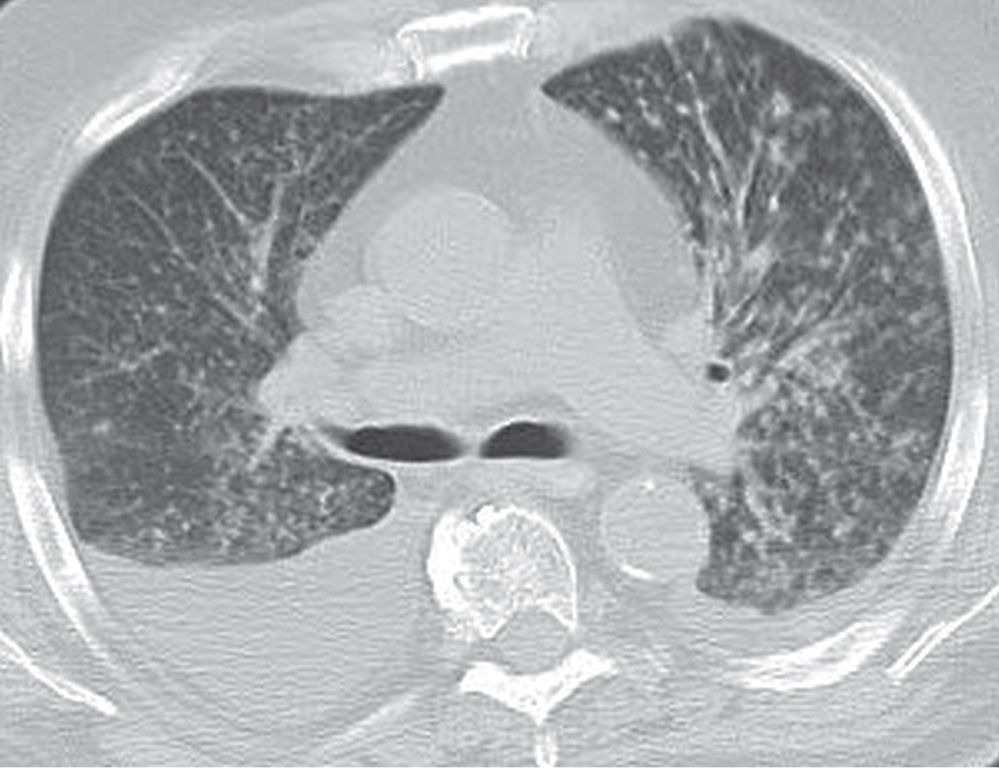

From radiologykey.com

Interstitial Lung Disease Radiology Key Lung Disease Common In Arizona Valley fever is becoming increasingly common, and it can be. The spores can survive through heat and drought, lingering in the. Valley fever is a respiratory disease caused by a fungus called coccidioides. Anyone in rural or urban areas of arizona can be infected by valley fever, though epidemiological investigations of patient charts show certain racial and ethnic groups are. Lung Disease Common In Arizona.